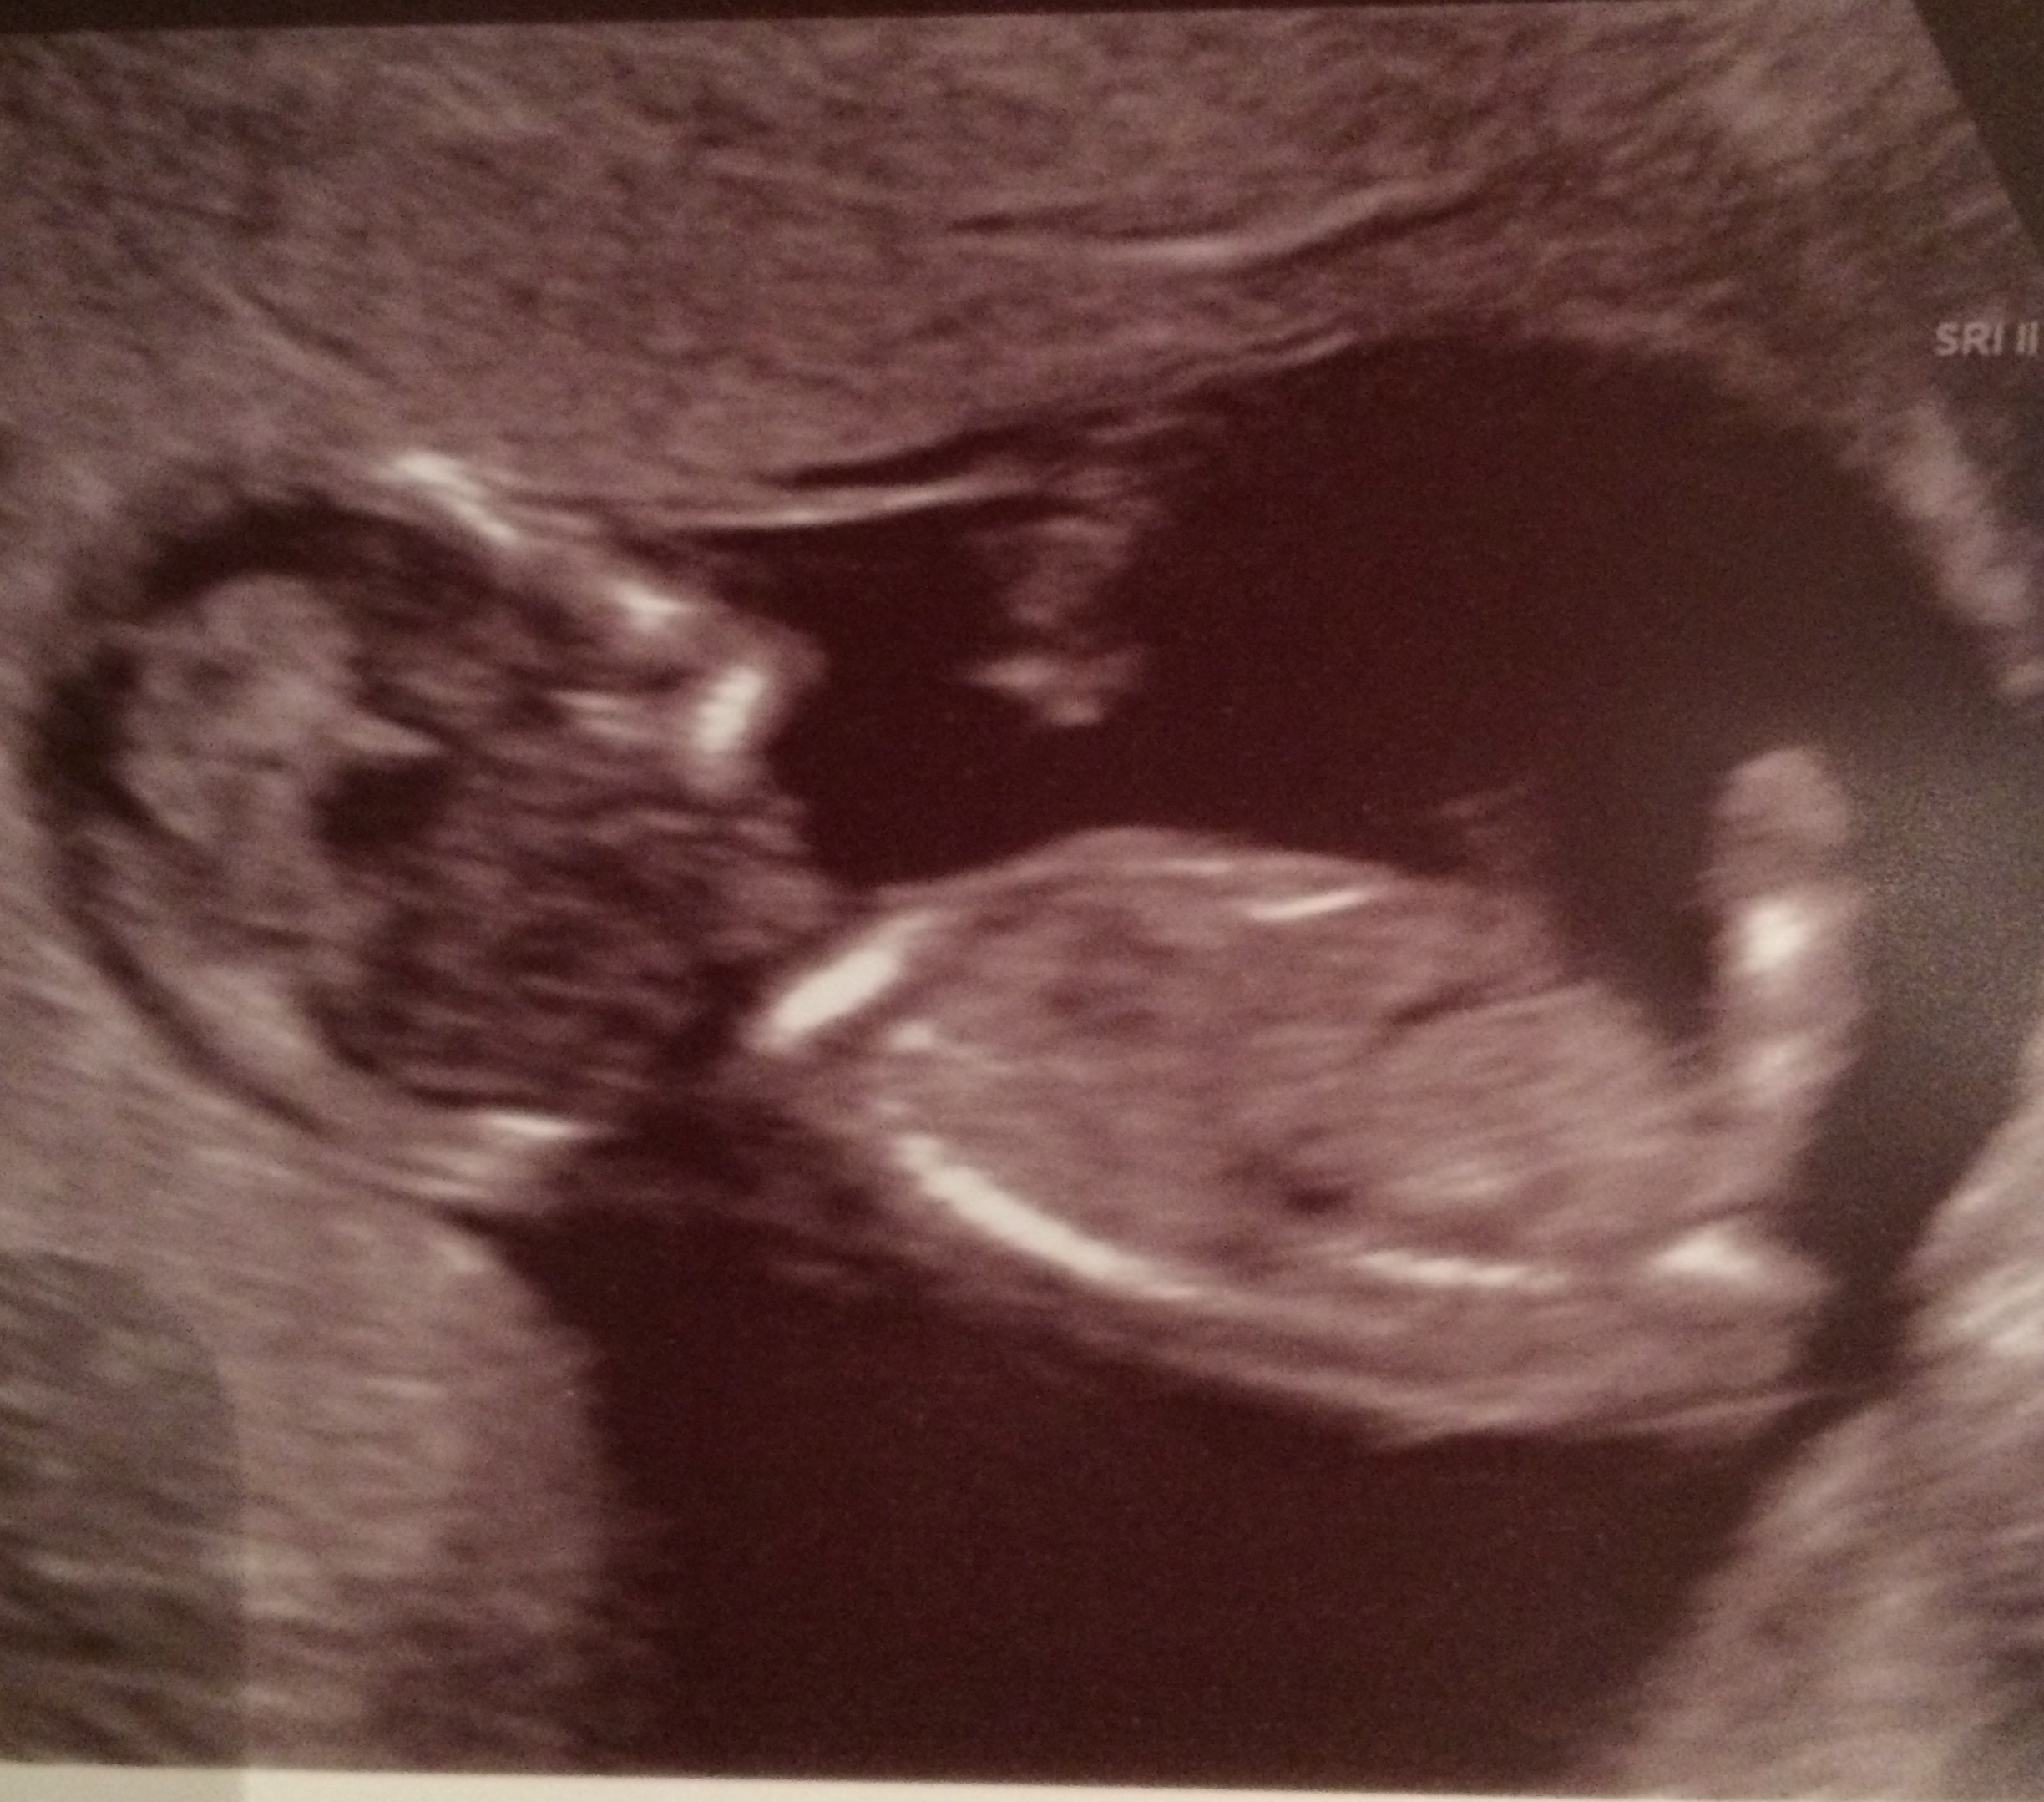

Hi! Do any of you experts have any idea what the sex of this baby is? It's from my 13 week scan -Thanks!

Nub is hiding in this one

I don't do skull hun as think it's a load of rubbish lol. Ultrasound images can change in seconds and can change until maturity. No nub isn't imaged unfortunately x